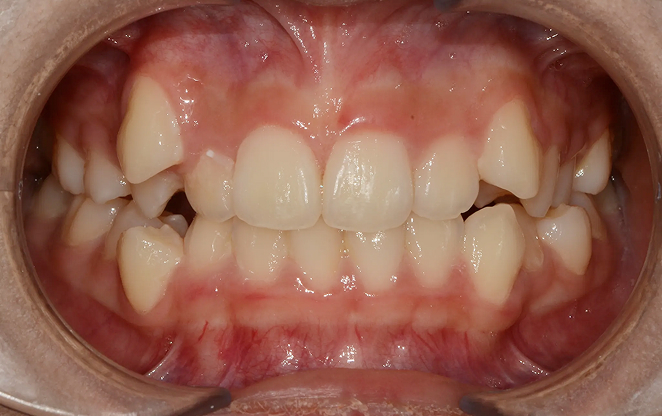

Before

After